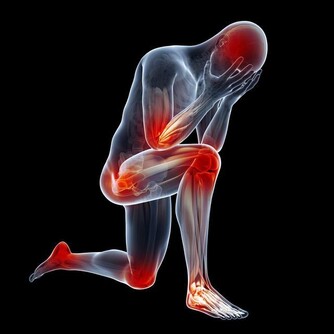

膝蓋復健術:最適合的運動方法

不管您現在有沒有膝蓋不舒服的情況,這個運動都會適合您,

因為這個運動:不需要外出,不需要器械,不損傷膝蓋,還能鍛煉到膝蓋!

方法:1)找一把可以靠背的椅子,臀部往後坐,靠著椅背。

雙手放在椅子背後,背部墊靠墊。

2)大腿下墊一條浴巾,也可以將幾條浴巾和毛巾捆綁在一起,只要夠厚、捆得紮實就可以,目的是要將膝蓋墊高。

3)坐姿端正,腰背挺直,兩腳垂放,一前一後地自然晃動。不需太大幅度擺動,輕輕鬆鬆地晃啊晃就可以了!

這一招看似十分簡易,對強化膝蓋卻非常有幫助。

舉個例子,如果每天可以晃到4000下,運動效果會比跑步更厲害!

膝蓋有舊傷或腳痛的人,可以用健康的腳去帶動痛的那隻腳,健康的腳托著痛的腳同時前後來回自然晃動,

這麼做相當於復健,可以讓膝蓋漸漸恢復健康。